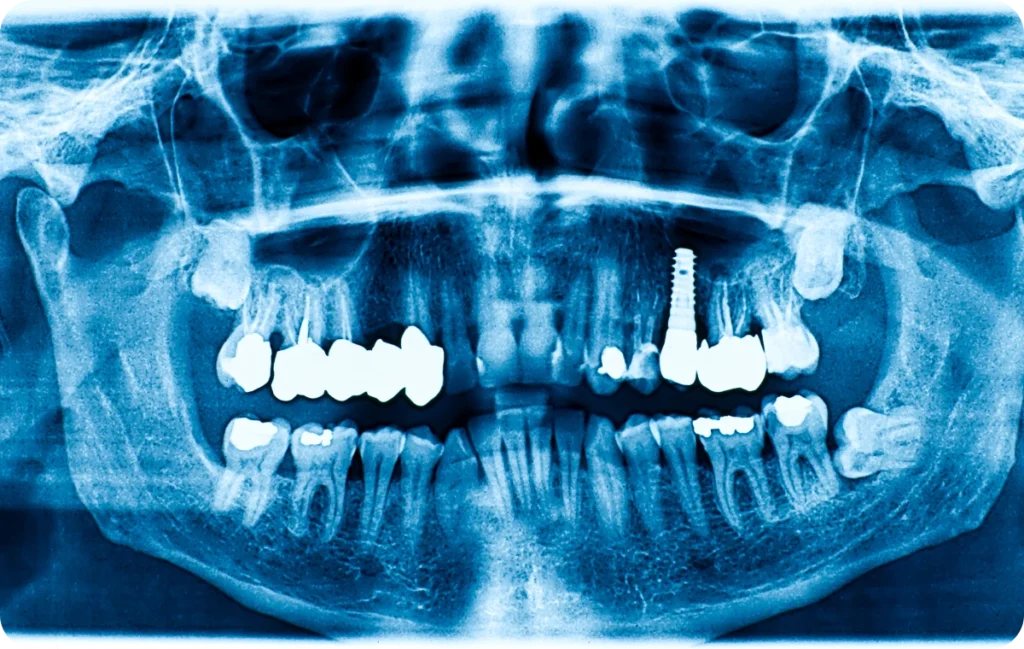

Un implant dentaire imite la racine d’une dent naturelle. Il s’ancre solidement dans l’os de la mâchoire. Sa fonction principale est de soutenir une couronne, une prothèse fixe ou amovible. De ce fait, il permet de retrouver l’esthétique d’un sourire complet et contribue à une meilleure mastication.

Un implant se compose de trois éléments clés : la vis en titane, qui se fixe dans l’os, le pilier sur lequel repose la couronne, et la couronne elle-même, souvent en céramique, qui imite l’apparence d’une dent. Le titane est choisi pour sa résistance et sa compatibilité avec les tissus corporels.

Avant la mise en place d’un implant, une évaluation complète est nécessaire. Cela comprend un examen dentaire et des radiographies pour évaluer la santé de la mâchoire et des dents avoisinantes. Un scanner 3D est souvent réalisé pour obtenir une vue détaillée de l’anatomie osseuse.